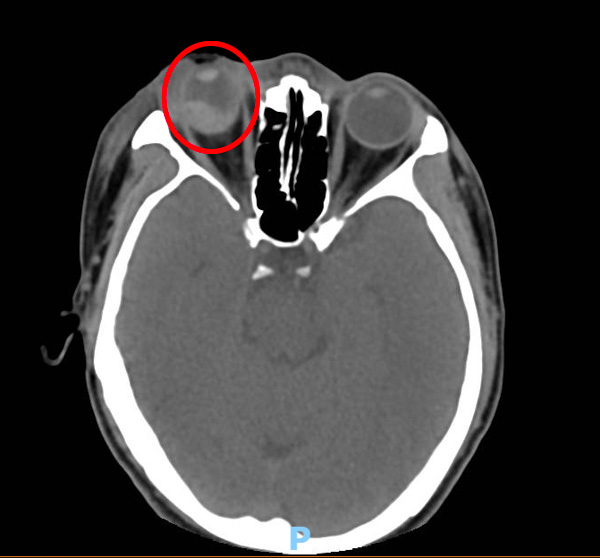

“当时患者的右眼伤得非常严重,我第一反应是眼球保不住的可能性非常大,很可能要装义眼。”柳州市人民医院眼科副主任医师付鹏回忆起第一次见到王先生的印象,通过B超检查,患者眼球里、视网膜下、脉络膜下全都是血,眼睛伤成这样,视功能肯定严重受损,但万幸的是患者的角膜没有伤到,那这只眼睛就有保住的希望!

王先生在得知情况后,也表达了想保住眼睛的强烈愿望,付鹏心中就更加坚定,一定要为患者保住这只珍贵的眼睛。2021年3月29号,他便为患者做了玻璃体切割手术,清除眼内出血,尽量复位视网膜和脉络膜,并填充硅油保持眼压,为之后植入人工玻璃体球囊创造有利条件。

由于王先生的右眼伤势严重,导致硅油依赖眼,需要持续眼内填充硅油才能维持眼压和眼球外形,不然可能会出现眼球萎缩,而硅油在眼内的一般填充时间为3-6个月,时间长容易变质乳化,需要定期置换。